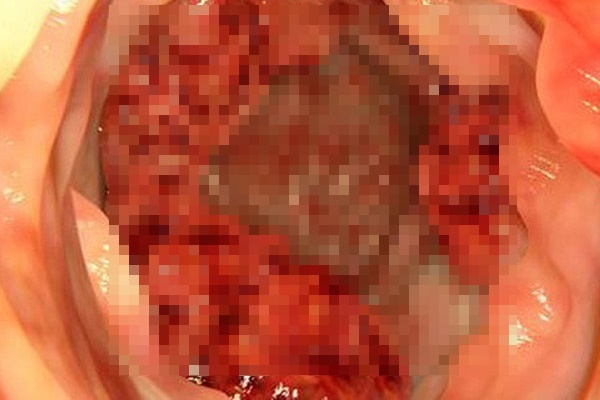

Ảnh minh hoạ.